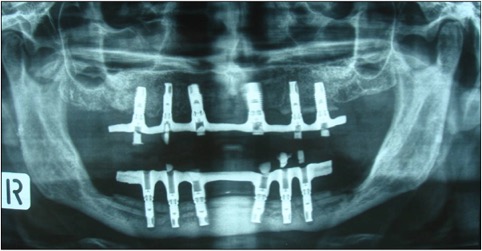

photo déroutement et greffe dans le même temps et résultat final avec implant.